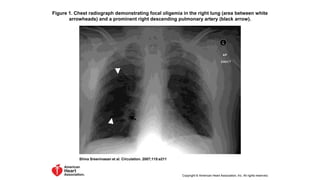

Chest X-ray Eponyms of PE

Westermark's sign

• Focal , demarcated oligaemia

• Hampton’s Hump

• A triangular or rounded pleural-based infiltrate with the apex toward the hilum,

usually located adjacent to the hilum.

• Palla’s sign

• prominent right descending pulmonary artery

Figure 1. Chest radiograph demonstrating focal oligemia in the right lung (area between white

arrowheads) and a prominent right descending pulmonary artery (black arrow).

Shiva Sreenivasan et al. Circulation. 2007;115:e211

Copyright © American Heart Association, Inc. All rights reserved.